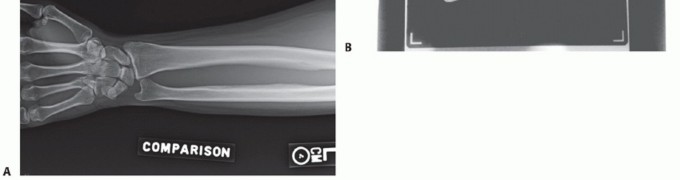

Axial loading may also rupture the interosseous membrane causing longitudinal radioulnar instability with dislocation of the distal radioulnar joint (DRUJ) (Essex-Lopresti fracture). An impacted radial neck or depressed radial head fracture should be highly suspicious of a concomitant interosseous membrane and DRUJ injury (FIG 4).

FIG 4 • AP x-ray showing a depressed articular fracture with impaction at the radial neck. This fracture pattern is highly suspicious for an Essex-Lopresti fracture. Radial head replacement is recommended. If ORIF is performed, the DRUJ should be stabilized to prevent instability.

Comminuted or impacted articular fractures (see FIG 4) are optimally managed with prosthetic replacement. Represents approximately 3% of radial head fractures18